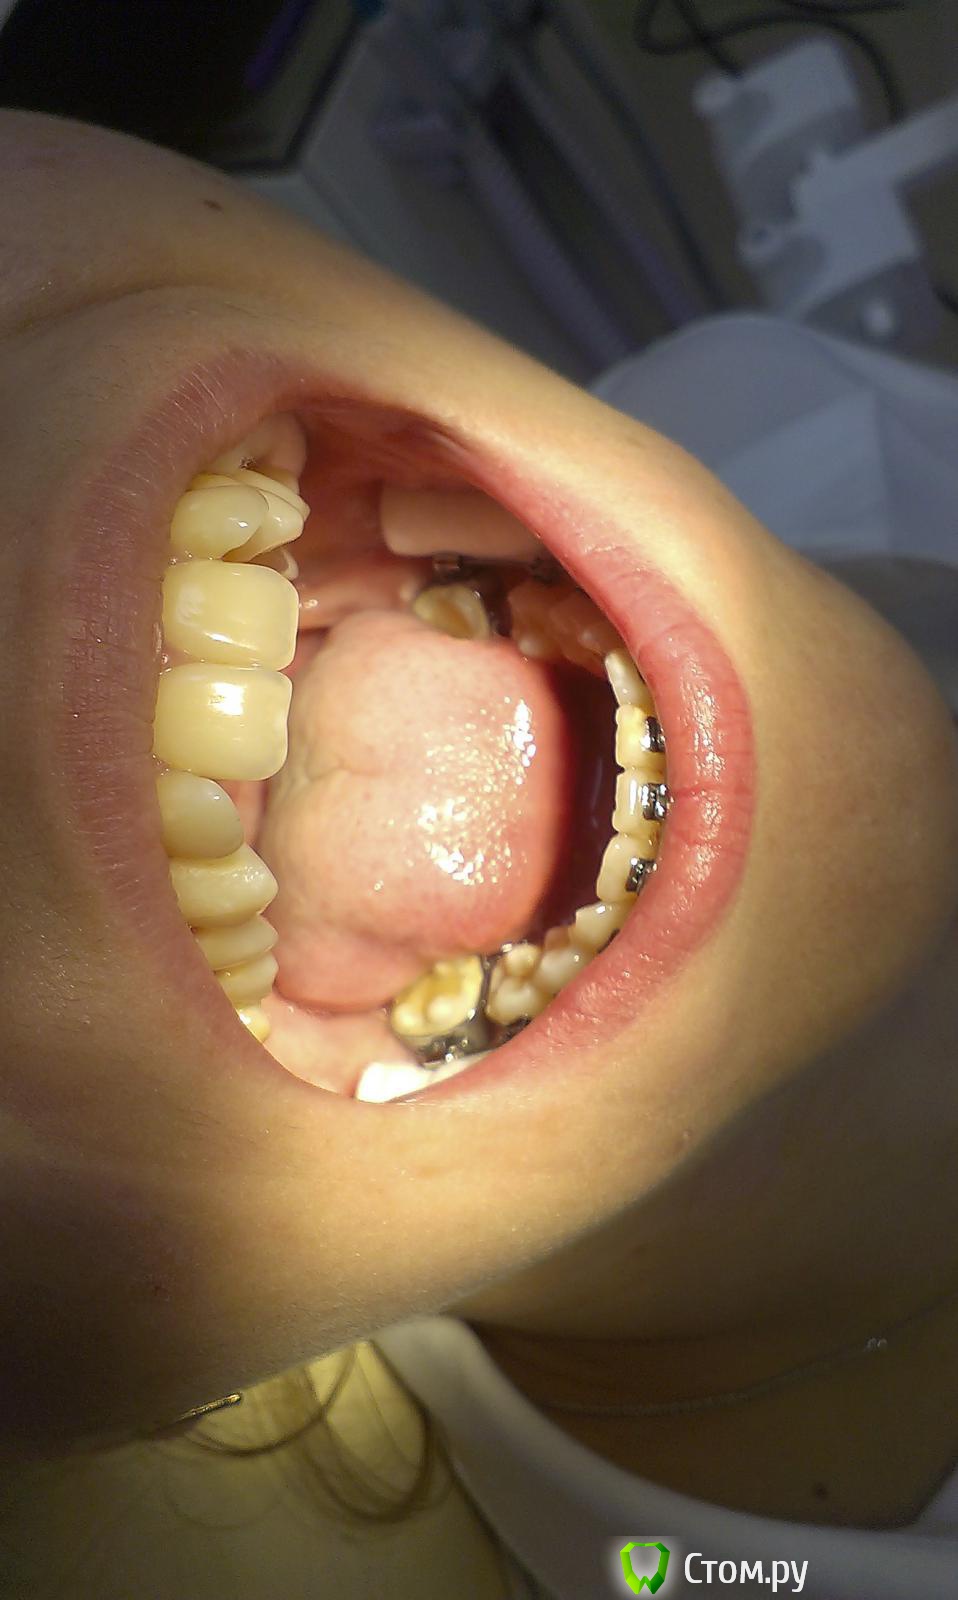

innessa Опубликовано 23 апреля, 2014 Поделиться Опубликовано 23 апреля, 2014 Здравствуйте. Ищу помощи и возможности принять правильное решение в лице стом.ру. Моя ситуация такова: мне 23 года, 1 год и 4 мес. прошло с тех пор, как мне установили брекет систему на нижнюю челюсть, перед этим удалив нижние шестые зубы. На ОПТГ картина 1 мес. назад.мой доктор-ортодонт рекомендует мне теперь удалить верхние четвертые зубы и продолжать ортодонтическое лечение.Что меня беспокоит, четвертые зубы абсолютно здоровы, в отличии от шестых и седьмых ( верхняя челюсть); была на консульт. и у других специалистов этой отрасли- у каждого свое мнение по поводу дальнейшего плана лечения и все они разные. помогите принять верное решение! Ссылка на комментарий

Ayrat_zub Опубликовано 5 мая, 2014 Поделиться Опубликовано 5 мая, 2014 Вам очная консультация больше поможет,в кратце-нужно работать с наклоном зубов, но резцы особо нужно проконтролироватьположением нижней челюсти,врехнюю челюсть включать надо было первой, либо одновременно ищите ортодонта который более подробно спланирует лечение... Ссылка на комментарий